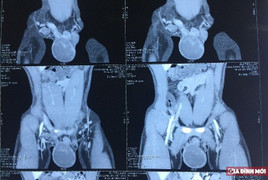

Lấy vợ một năm vẫn chưa có con, trong khi tinh hoàn phải ngày càng to dần, đau tức, bệnh nhân nam buộc lòng đến bệnh viện kiểm tra.